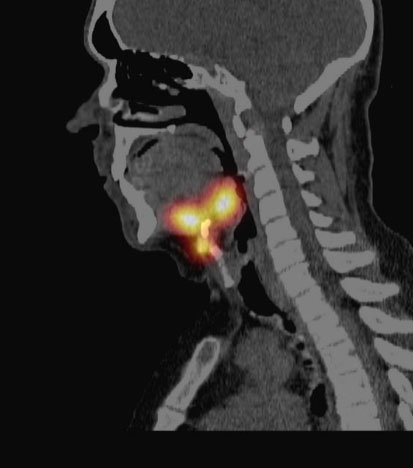

A 46-year-old male with a past medical history of hypothyroidism and cannabis use disorder presented to his primary care physician with a globus sensation and left cervical lymphadenopathy for two weeks. A computed tomography (CT) scan of the neck with contrast identified three high attenuation areas: the first in the midline floor of the mouth extending posteriorly to the base of the tongue (1.5 × 2.2 cm) (Figure 1), the second at the base of the tongue (1.4 × 1.8 × 3.0 cm) (Figure 2), and the third in the midline of the neck just beneath the hyoid bone (1.3 cm) (Figure 3). Thyroid tissue was not identified in the orthotopic location (Figure 4). A follow-up thyroid uptake and scan confirmed that each of these high attenuation areas was also iodine avid, consistent with thyroid tissue (Figure 5). Notably, there was no uptake in the normal orthotopic thyroid location.

Figure 5: Thyroid uptake and scan confirming the three iodine-avid areas consistent with ectopic thyroid tissue. Notably, there is no uptake in the normal orthotopic thyroid position.

In the reported cases of triple ectopic thyroid, the most common locations were the lingual (88%) and suprahyoid (88%) regions [1],[2],[3],[4],[5],[6],[7]. Less common locations included the infrahyoid (50%), pre-tracheal (25%), and cricoid cartilage (13%) areas [1],[2],[3],[4],[5],[6],[7]. Lastly, one patient only had ectopic thyroid lateral to the orthotopic thyroid [8]. In addition to lingual (Figure 1) and infrahyoid (Figure 2) areas, our patient had ectopic thyroid in the midline mouth (Figure 3) which has not previously been described and would seem quite unusual given the embryological pathway in normal thyroid development.